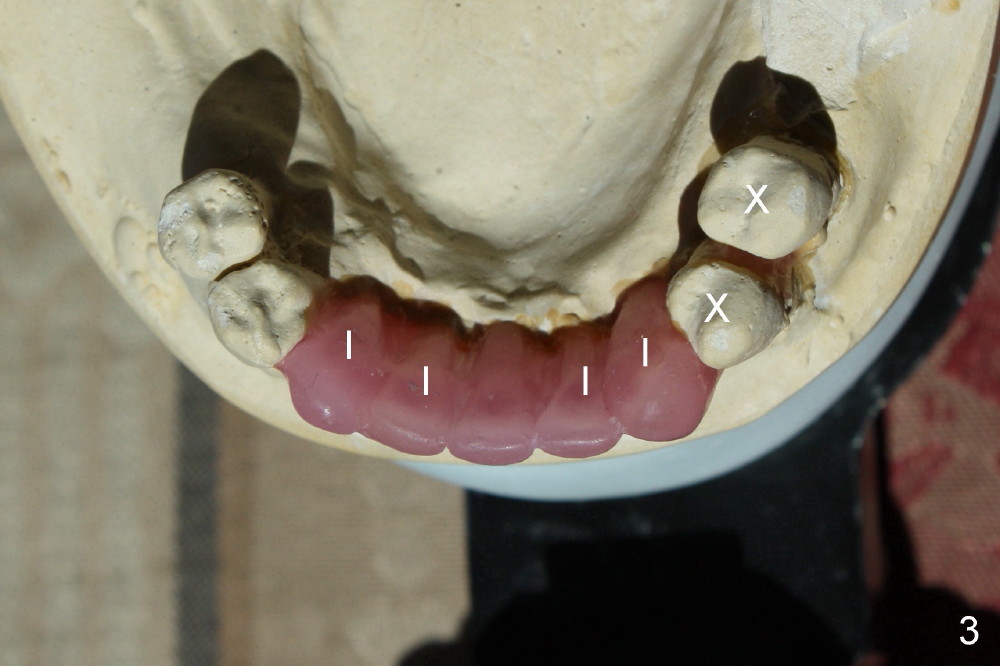

A 52-year-old man seeks treatment 2 months following loss of #22-27 fixed partial denture (FPD) (Fig.1,2).  The remaining dentition has moderate to severe chronic periodontitis.  Scaling & root planing has been done for the upper arch.  Full mouth reconstruction is planned for the lower one in two steps.  In the first procedure, the teeth #18, 20 and 21 are extracted; an incision is made from #20 to #27; two immediate implants are placed at the sites of #20,21 (one or two piece, Fig.3,5 X); another two implants at #22,27 (recently healed sites: Fig.3-5: I) and two one piece implants at lateral incisor region (I: for an implant supported FPD).  In case one of the lower left premolars cannot have an implant due to proximity to the nerve, a FPD can be fabricated in the canine/premolar sextant. A splinted immediate provisional restoration will be fabricated from #20-27 immediately.